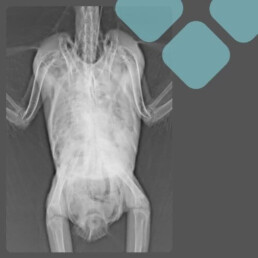

K dalším onemocněním, u kterých aplikace antibiotik nevyřeší primární problém, patří například zadržení snášky, pozření cizích těles nebo ztučnění (lipidóza) jater. V těchto případech je nutné provést rentgenologické vyšetření, které nám napomůže odhalit problém a stanovit následnou léčbu.